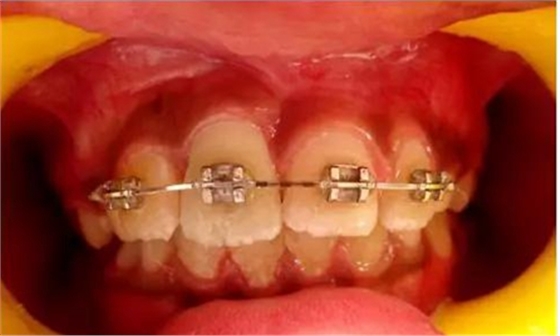

健康的 7 歲男童,前一天摔倒,上頜右中切牙和右側(cè)切牙發(fā)生挫入脫位(圖 1)。無(wú)牙外傷史,無(wú)神經(jīng)并發(fā)癥病史。檢查發(fā)現(xiàn)雙側(cè)下頜下腺增大。

口腔內(nèi)發(fā)現(xiàn):混合牙列早期,覆蓋正常,安氏I類磨牙關(guān)系。牙11和12齦緣紅腫。

牙11,12 和21對(duì)叩診敏感。牙11嚴(yán)重挫入(牙11和牙12的切緣相差7毫米),并挫入牙槽窩。與牙21相比,牙12大約挫入4毫米。

正畸牽引觀察其復(fù)位情況: 先觀察挫入的牙齒在未干預(yù)的情況下自發(fā)復(fù)位的情況。經(jīng)過(guò)3周的觀察,牙12復(fù)位,但牙11沒(méi)有顯示出復(fù)位的跡象。因此,使用MBT托槽正畸牽引牙11復(fù)位。為了讓其沿正確的方向復(fù)位,使用橡皮圈以獲得緩慢持續(xù)的牽引力(圖3)。

(圖3)